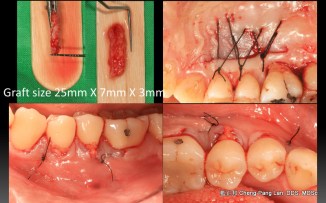

Root Coverage – Coronally Advcanced Flap with Connective Tissue Graft- Case B

Recipient Site: Harris’s technique, 1992

Donor Site: Bruno’s technique, 1994